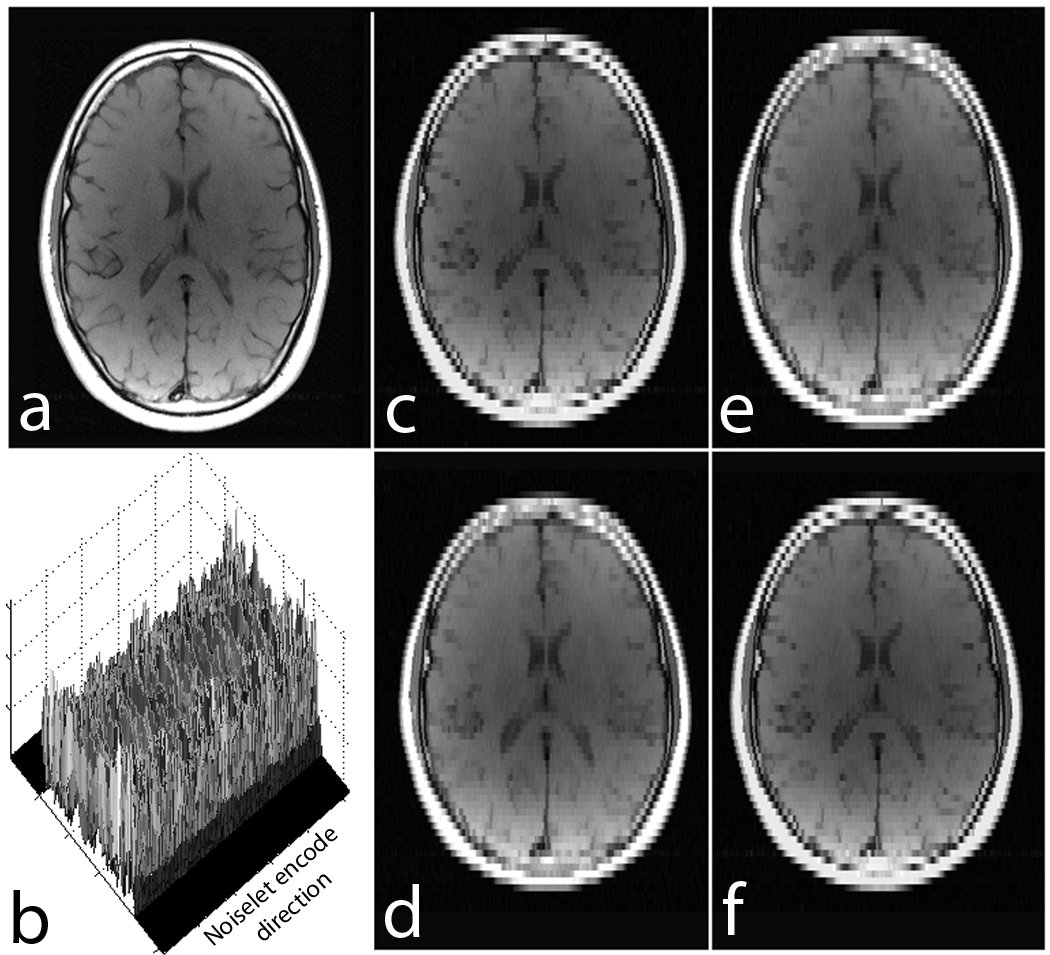

Noiselet transform is a type of Haar-Walsh transform. The noiselet transform coefficients totally spread out the signal in scale and time (or spatial location) [35]. As a result, each subset of the transform coefficients contains a certain information of the original signal at all the scales and times (spatial locations), and can be used alone with zero padding to reconstruct the original signal at a lower resolution. This important property is demonstrated by the example shown in Fig. 2.

Fig. 2 shows a brain image of size , and the 3D magnitude map of the noiselet transform of the brain image along the phase encoding direction (all noiselet encodes). Fig. 2 (c-f) shows the images reconstructed with the first, second, third and fourth 64 noiselet encodes by zero padding the rest. Each of these images are reconstructed using one quarter of the noiselet encodes and has low resolution than the original image. However, each of these images have complementary information about the original image and have approximately the same amount of energy and information because they are reconstructed using the same size of partial matrix from the original coefficient matrix.